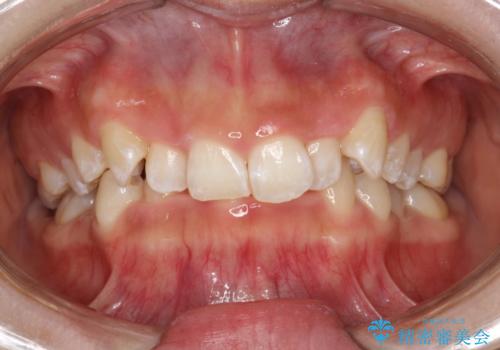

矯正治療開始前のPMTC

- 矯正治療前にステインを取りたいとのことで来院されました。ステインは前歯のみだったため、PMTC30分コースを行いました。

PMTCとは、歯科の専門家が器械を使用して行う歯のクリーニングのことです。普段の歯磨きでは取り切れない溝、キワなどの細かい部分も徹底的に除去します。ステインや歯石などが付着したままだと、虫歯や歯周病の発見がしずらいことがあります。特に矯正治療前には、念入りな虫歯や歯周病チェックが必要なため、PMTCでしっかりと汚れを除去しておくことが大切です。